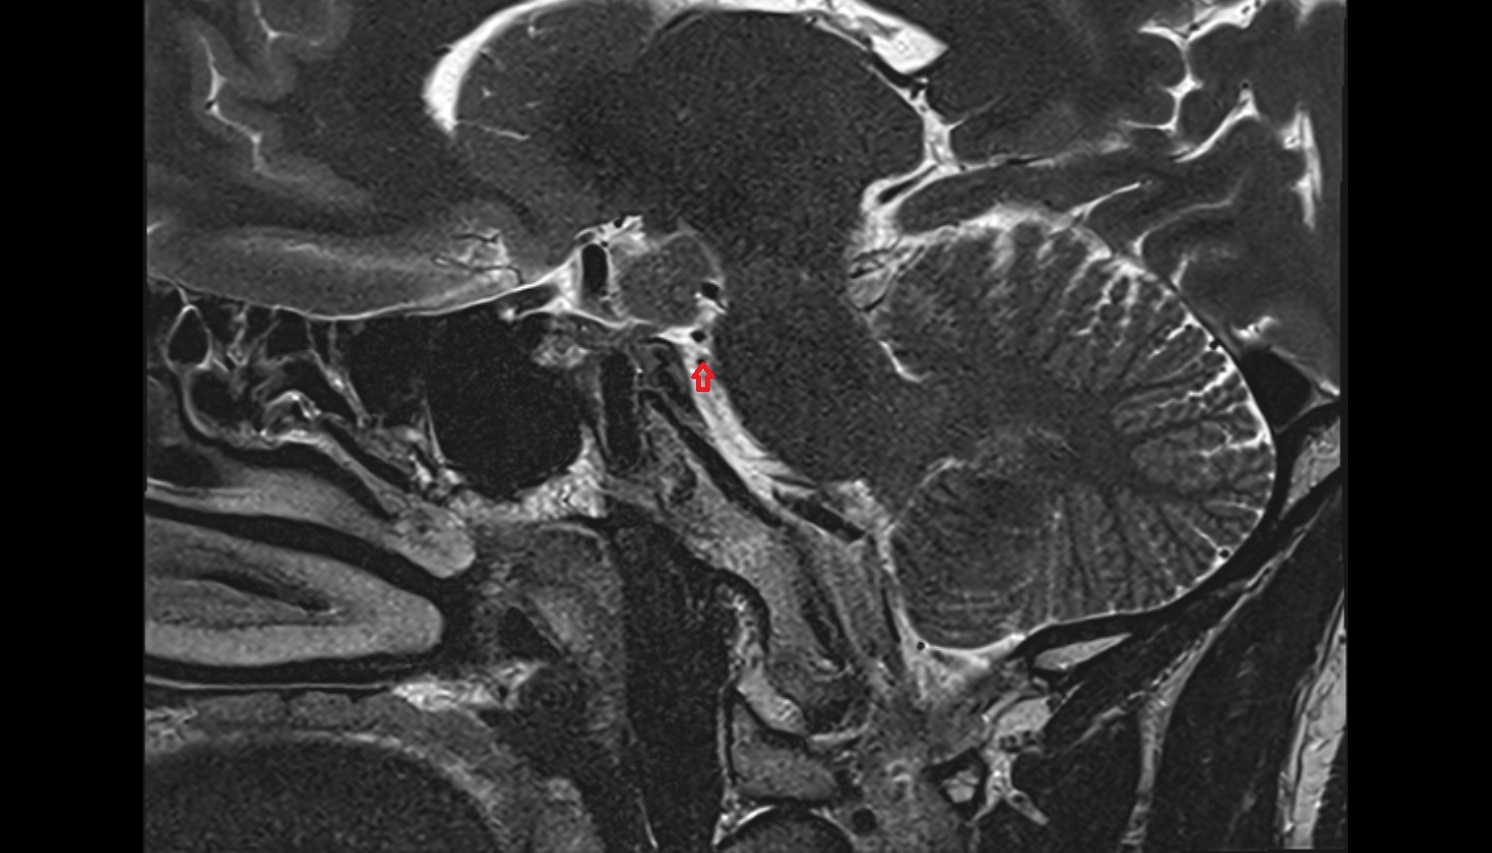

- Temporomandibular joint

- Articular disc of temporomandibular joint

- Articular eminence

- Mandibular condyle

- Mandibular fossa